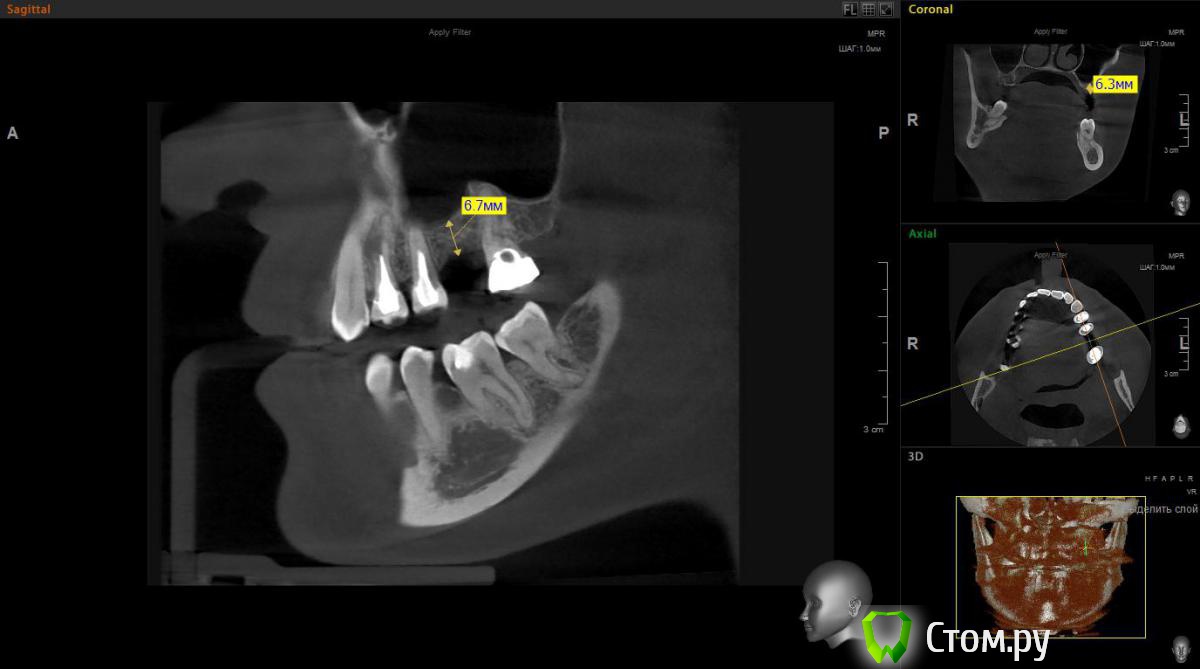

Евгений Ходыкин Опубликовано 1 ноября, 2014 Поделиться Опубликовано 1 ноября, 2014 Есть большое желание обойтись закрытым синусом в данной области. Ложе подготовить экспандерами, ими же поднять "дно". МР3 в пазуху (или чисто на сгустке оставить?). НРК по ситуации. Заранее спасибо за комменты Ссылка на комментарий

Евгений Ходыкин Опубликовано 1 ноября, 2014 Автор Поделиться Опубликовано 1 ноября, 2014 Колеблюсь между 8 и 10 длиной винта Ссылка на комментарий

red_butler Опубликовано 1 ноября, 2014 Поделиться Опубликовано 1 ноября, 2014 Есть большое желание обойтись закрытым синусом в данной области. Ложе подготовить экспандерами, ими же поднять "дно". МР3 в пазуху (или чисто на сгустке оставить?). НРК по ситуации. Заранее спасибо за комменты мне кажется замеры сделаны не корректно, вы мерили от края гребня.реальная высота около 3 мм, соответственно делать нужно открытый Ссылка на комментарий

victor57 Опубликовано 1 ноября, 2014 Поделиться Опубликовано 1 ноября, 2014 Я считаю открытый делайте.гребень узкий,при формировании ложа импланта часть кости уйдет и,действительно,останется 3-4 мм Ссылка на комментарий

red_butler Опубликовано 1 ноября, 2014 Поделиться Опубликовано 1 ноября, 2014 (изменено) а откуда тогда нужно замерять, пардон?? там где ширина позволяет поставить винт, на вершине гребня ширина около 1.5 мм. поставьте в проге виртуальный имплант Изменено 1 ноября, 2014 пользователем red_butler Ссылка на комментарий

Чертков Александр Опубликовано 2 ноября, 2014 Поделиться Опубликовано 2 ноября, 2014 Жень, некорректно промерил...там 3-4 мм, я за открытый. Возможно сразу с винтом. По ситуации. Ссылка на комментарий